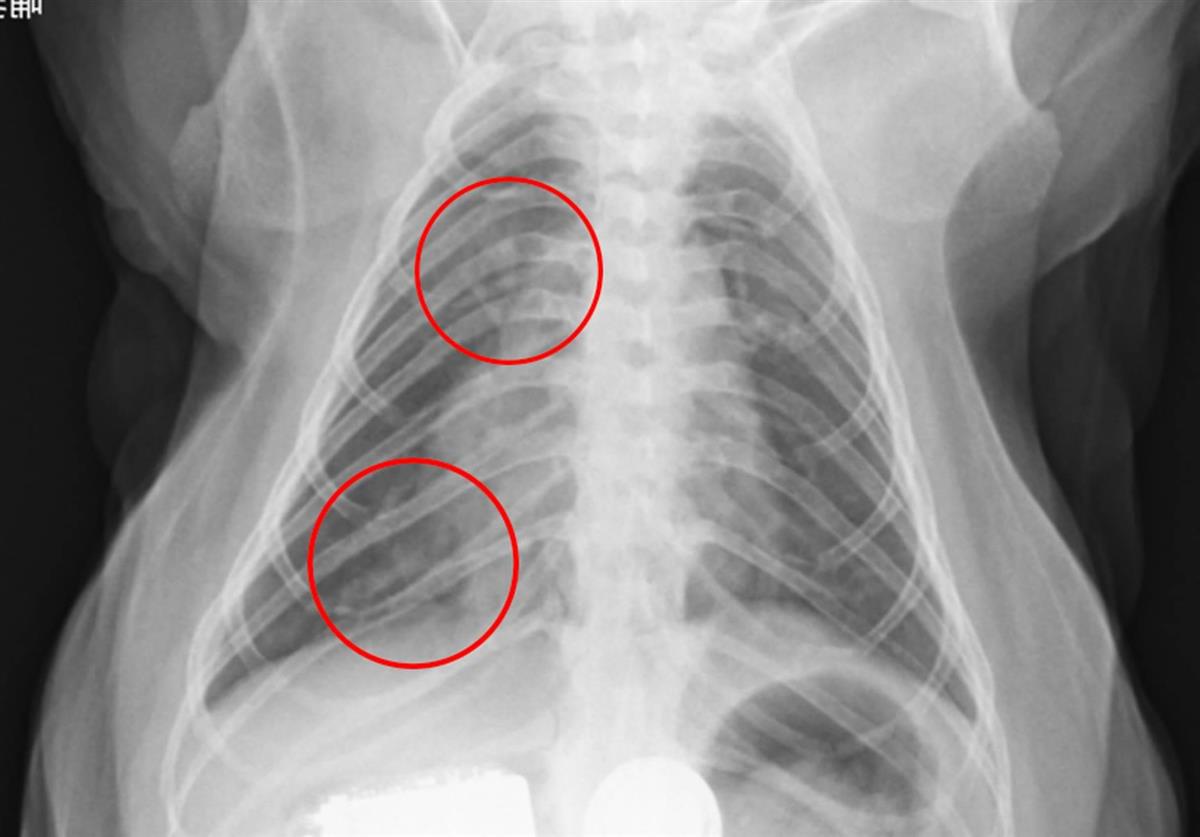

実験では10~15歳の大人のカニクイザル3頭に新型コロナウイルスを投与したところ、約1週間にわたって鼻や口からウイルスが検出されたほか、発熱や肺炎などの症状がみられた。いずれも軽症で治まった。

また、感染者の重症化リスクとして指摘されている肺における血栓(血液の塊)の形成も確認。新型コロナの実験動物として現在広く使用されているハムスターでは再現できなかった症状で、29日に滋賀県庁で記者会見した伊藤教授は「より人に近い症状が出ることを確認できた」と説明した。